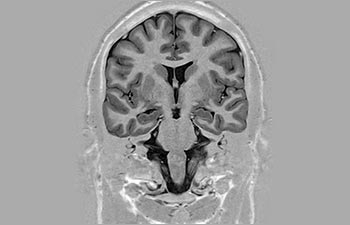

La Sra. Silvia Schiffer, directora y radióloga experta en la clínica Radiologie Schiffer, en Alemania, comparte sus experiencias con el sistema de RM Prodiva 1.5T.

Conozca la opinión de los primeros usuarios de Ingenia Prodiva 1.5T acerca de sus experiencias con el sistema y cómo influye este en su centro de diagnóstico por imagen.